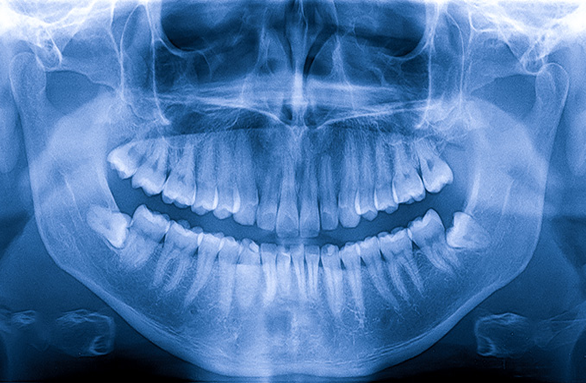

RVG

Elite Smiles Dental Care is one of the very few dental clinics in Ulwe to carry out Dental Implants. We have an in-house Implant specialist who works exclusively on implants. Our years of experience and up to date technology like Oral Scanners, CAD/ CAM and OPG makes us the perfect candidates to do a perfect job.